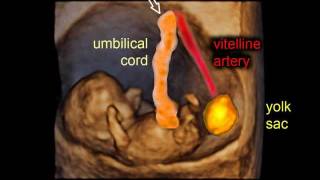

Ultrasound showing a 9 weeks fetus with no Heart Beat 9 weeks of pregnancy: gestational sac and embryo - 3D scan

9 weeks of pregnancy: gestational sac and embryo - 3D scan ✅1To 9 Month Baby Pregnancy |Fetal Development In Womb| #fetus #baby #pregnancy #viralvideo #love